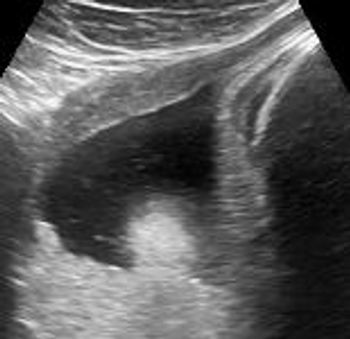

This second-trimester fetus has a renal abnormality. Can you identify it?